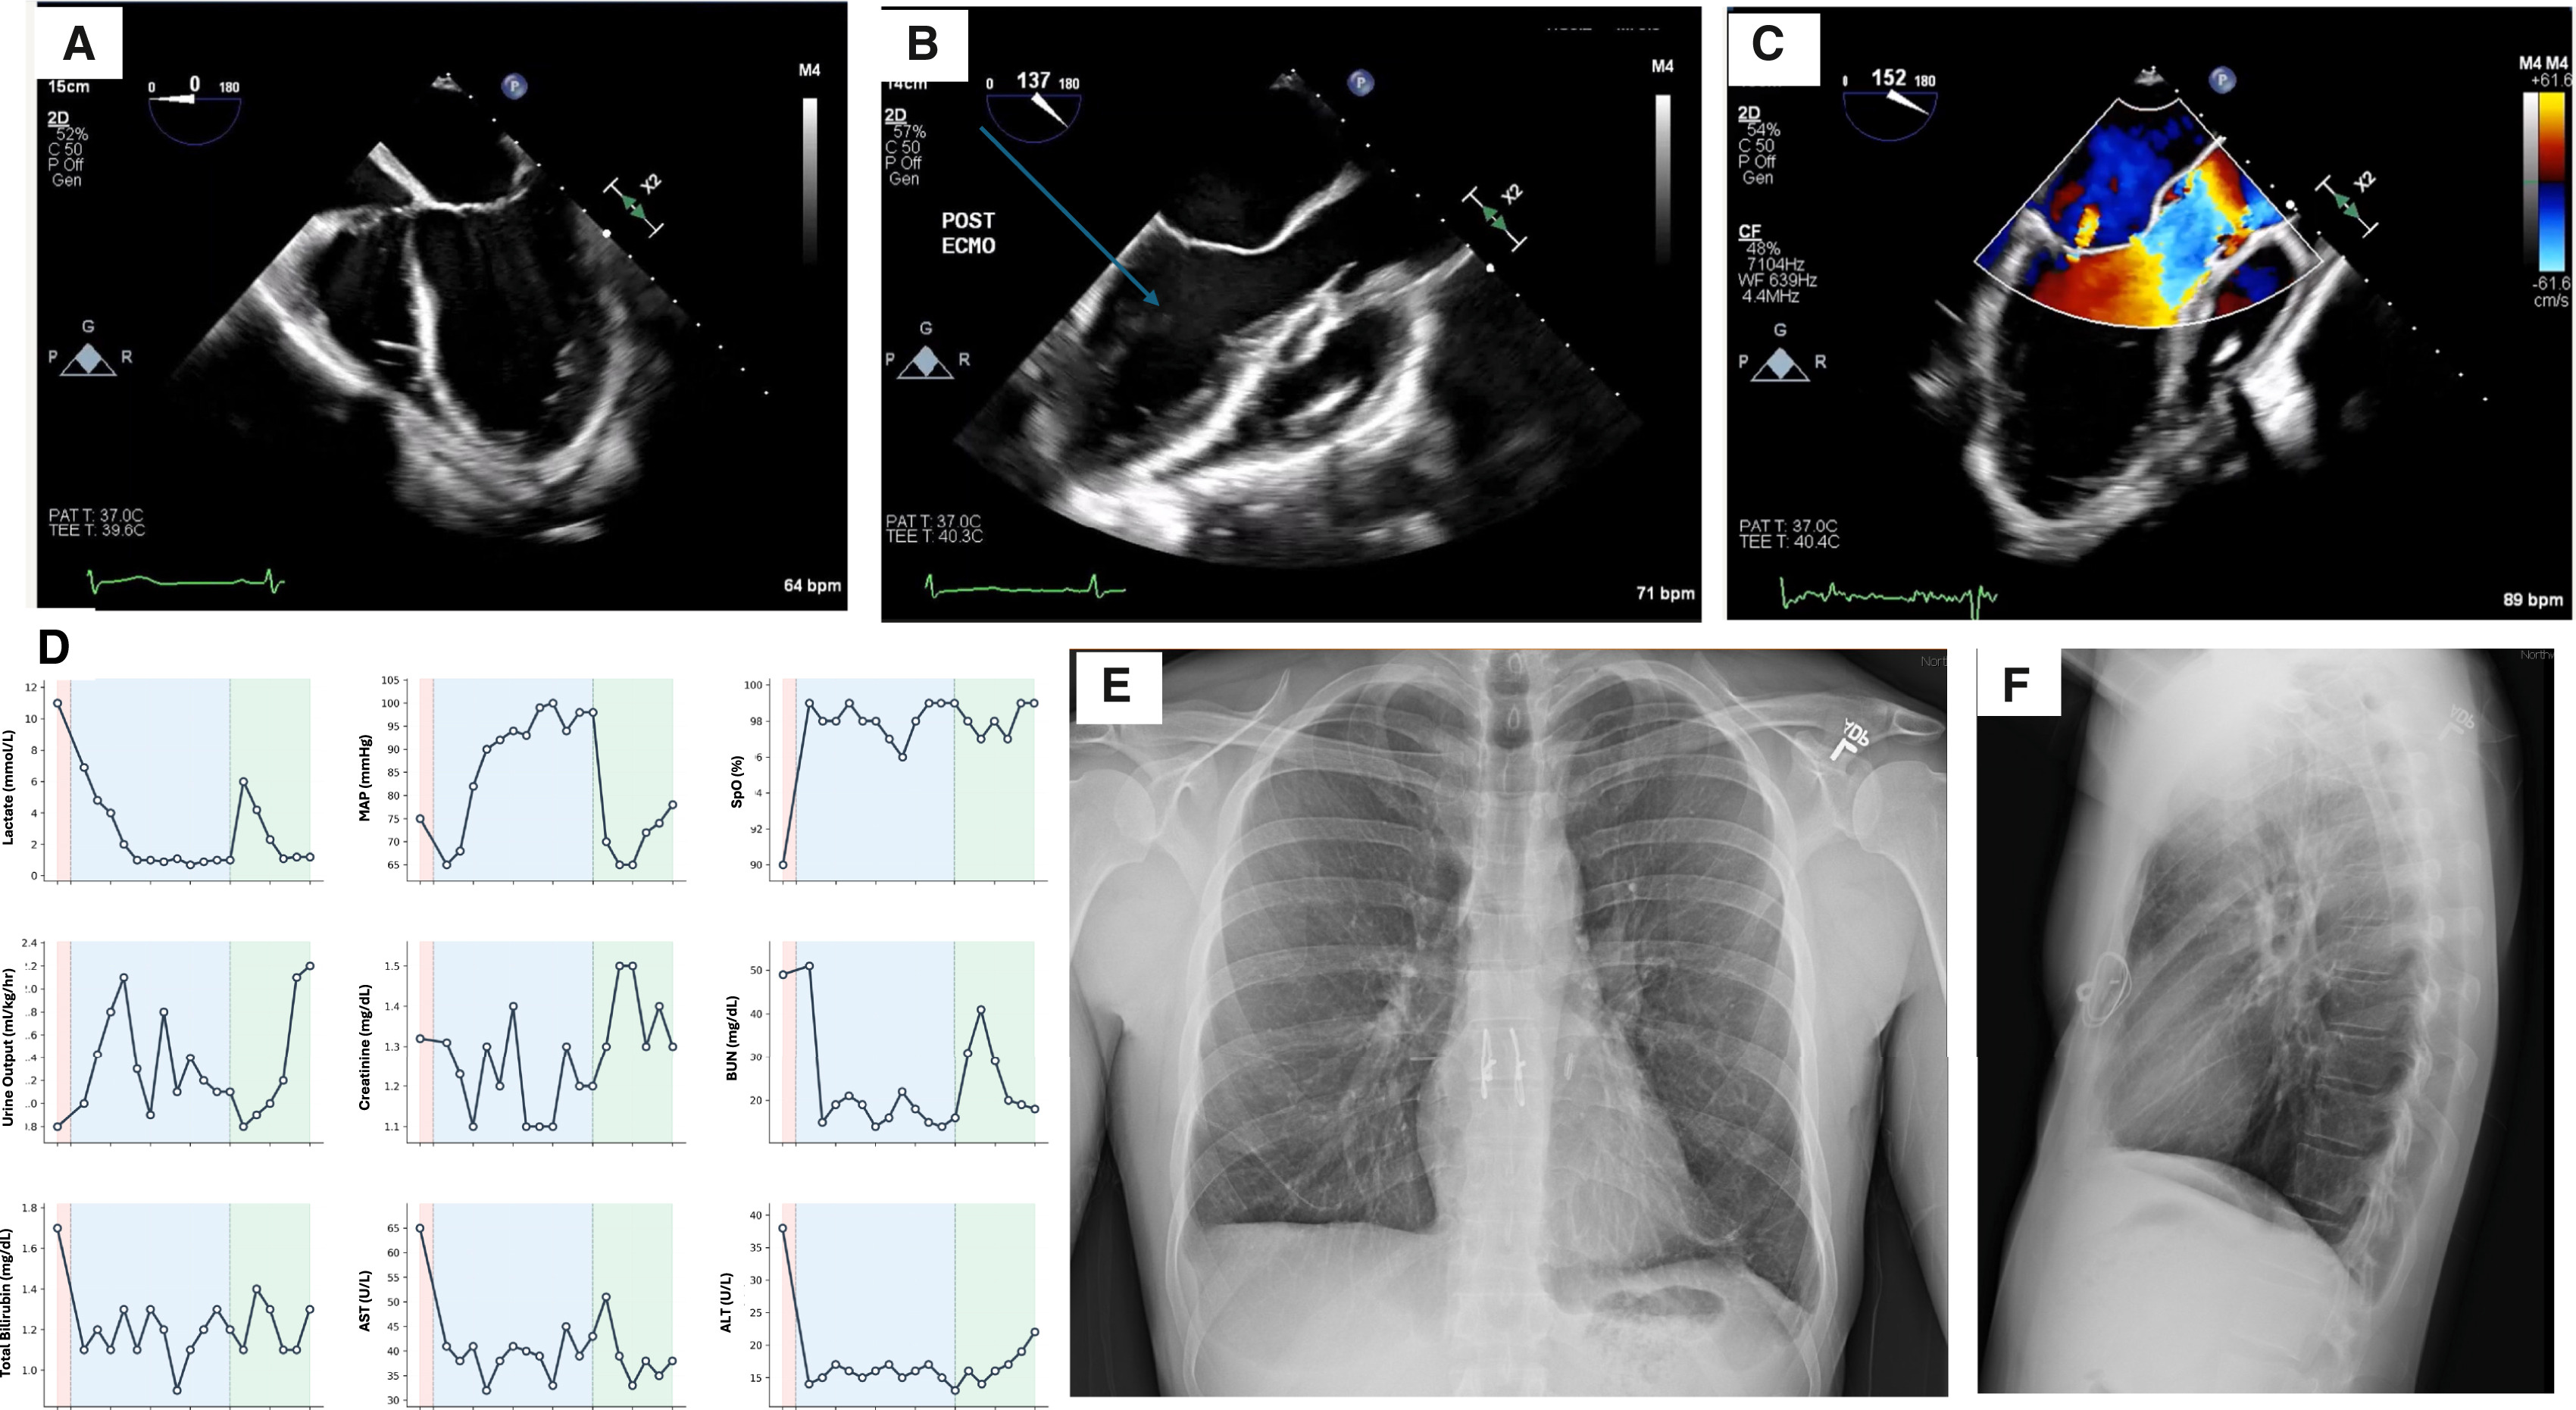

The custom TAL system functioned as a complete circulatory bridge, using specialized shunts and external units to oxygenate the blood and scrub carbon dioxide. More than just a breathing machine, it featured dual return lines that carefully regulated blood flow back to the heart, ensuring the organ remained stable and continued to pump naturally even with the lungs missing.

The results were immediate. Once the infected lungs were removed, the source of the sepsis vanished. Within 48 hours, the patient's blood pressure stabilized, his kidney function returned to normal, and he no longer required medication to keep his heart beating.

While the patient was supported by the machine, researchers analyzed his removed lungs. They discovered "irreversible injury," with the normal air sacs completely replaced by scar tissue and inflammatory cells, proving that a transplant was his only hope for survival.